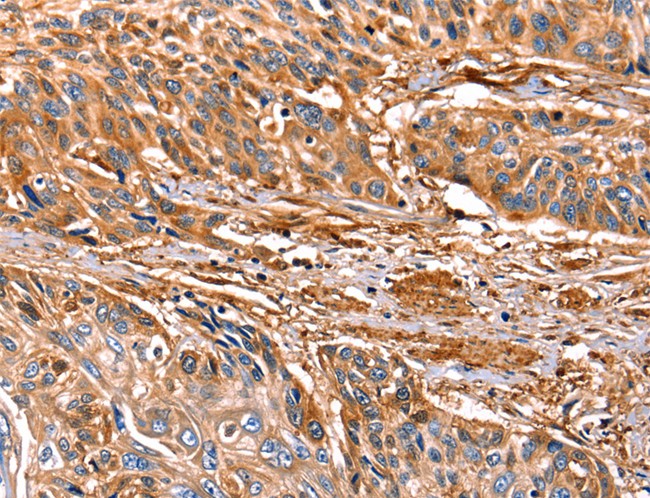

IHC (Immunohiostchemistry)

(LMO2 Antibody (N-term) immunohistochemistry analysis in formalin fixed and paraffin embedded human brain tissue followed by peroxidase conjugation of the secondary antibody and DAB staining.This data demonstrates the use of LMO2 Antibody (N-term) for immunohistochemistry. Clinical relevance has not been evaluated.)